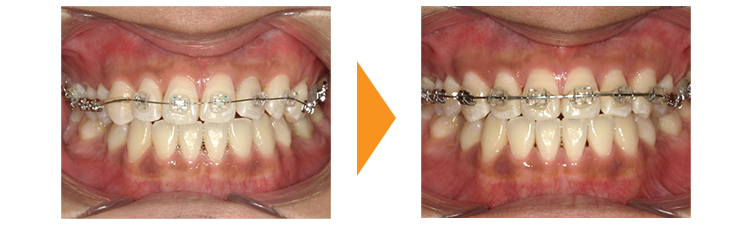

マウスピース矯正でのトラブル症例です。

マウスピース矯正が普及してる一方で、マウスピース矯正のトラブルが非常に多くなっています。

この患者様は〇〇〇ラインというマウスピース矯正で費用も全額お支払いになっており、これで終了と言われたが、歯のねじれが残っていることを主訴に来院されました。

費用のことや、治療期間、矯正中や矯正後に神経の処置やかぶせ物の治療といった一般歯科治療が必要であり歯の形が変わってしまうことを踏まえ患者様と相談したうえ、ワイヤーの部分矯正にて対応した症例です。

実際に矯正器具を付け歯を動かしていくと、右上の犬歯がかなり「動きにくい」状態でした。

ワイヤー矯正のメリットは24時間力を持続的にかけ続けられることですが、それでも歯が動く量が通常よりもかなり少なく移動にかなりの時間を要しました。

この患者様がもし当院でマウスピース矯正のような取り外しが可能な装置で最初治療を開始したとしてもうまくいかなかっただろうなと思います。実際に歯を動かしてみて「歯が動きにくい」ことがわかることもあります。このような方がマウスピース矯正を行っていて途中で「歯が動かない」状況になった場合はワイヤー矯正に切り替えるなどの対応が必要となります。「矯正治療で歯が動かない」ことについてはこちらのブログも参照してください。

| 初診時 | 26歳男性 |

|---|---|

| 主訴 | 他院でマウスピース矯正をしたがガタガタが治っていない |

| 期間 | 約10か月 |

| 矯正 | ワイヤー矯正 |

| 費用 | 基本検査22,000円・契約料220,000円・調整料5,500円/月(税込) |

| 治療上のリスク | 歯磨き不良の場合はむし歯になる可能性。 習癖に伴う後戻りの可能性。 |